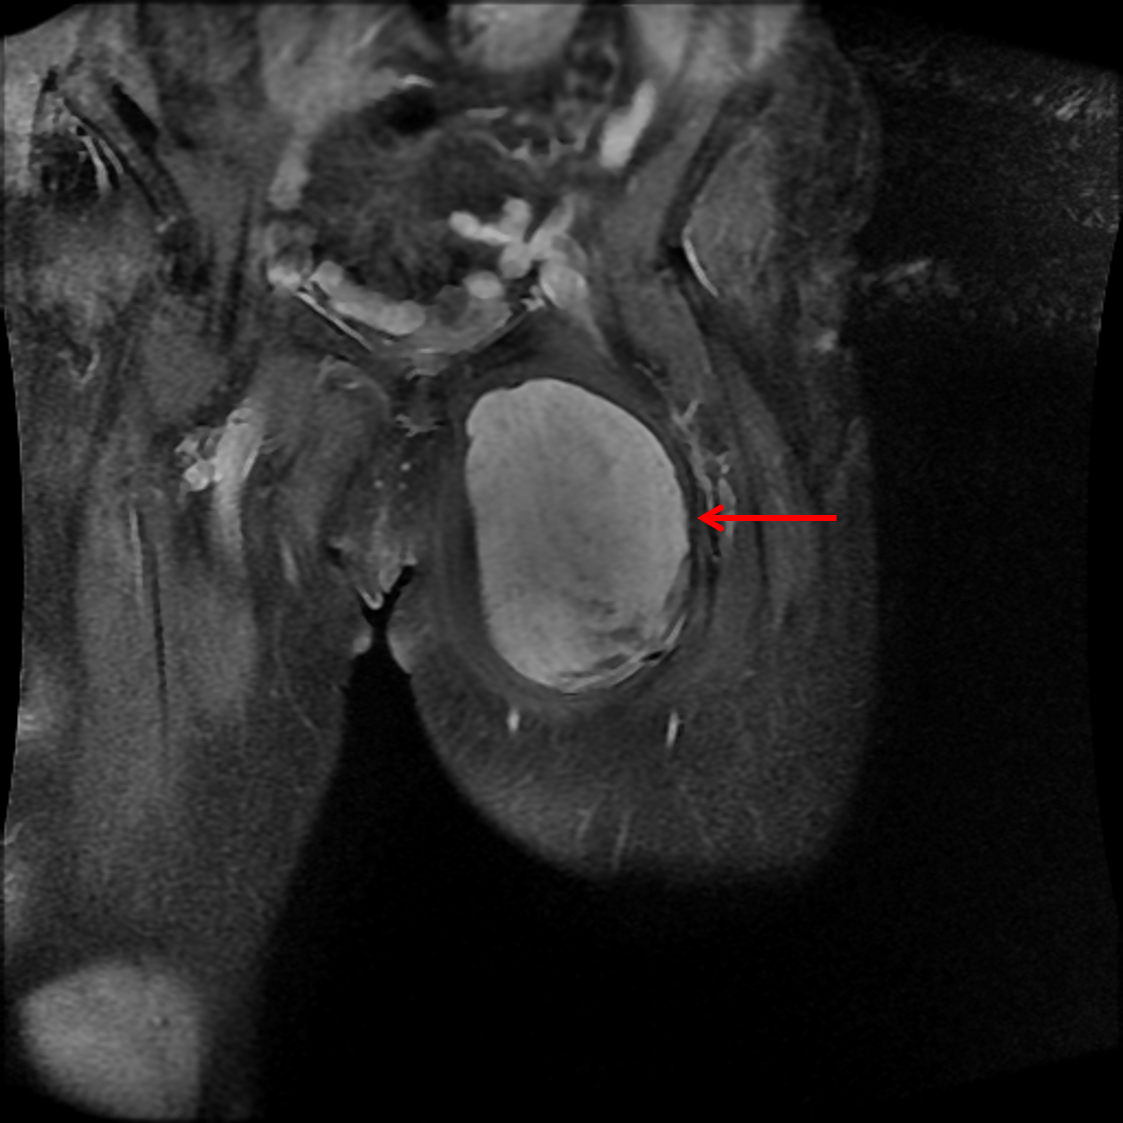

Age: 81

Sex: Female

Indication: Left thigh injury

Soft tissue neoplasm (solitary fibrous tumor)

Sample ReportSolid mass in the anteromedial left thigh measuring 12.2 x 5.6 x 11.7 cm, which demonstrates internal vascularity and is concerning for neoplasm. Recommend MRI with and without contrast for further assessment of the mass and of the extent to which it involves adjacent structures.